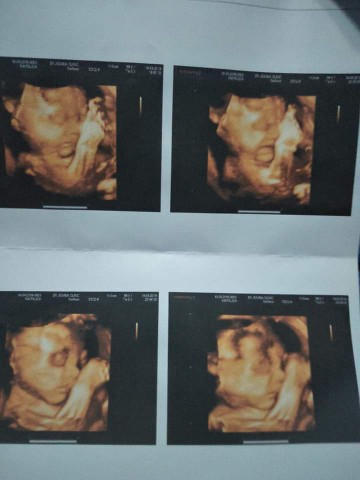

29wจ้า

29wแล้วค่ะ